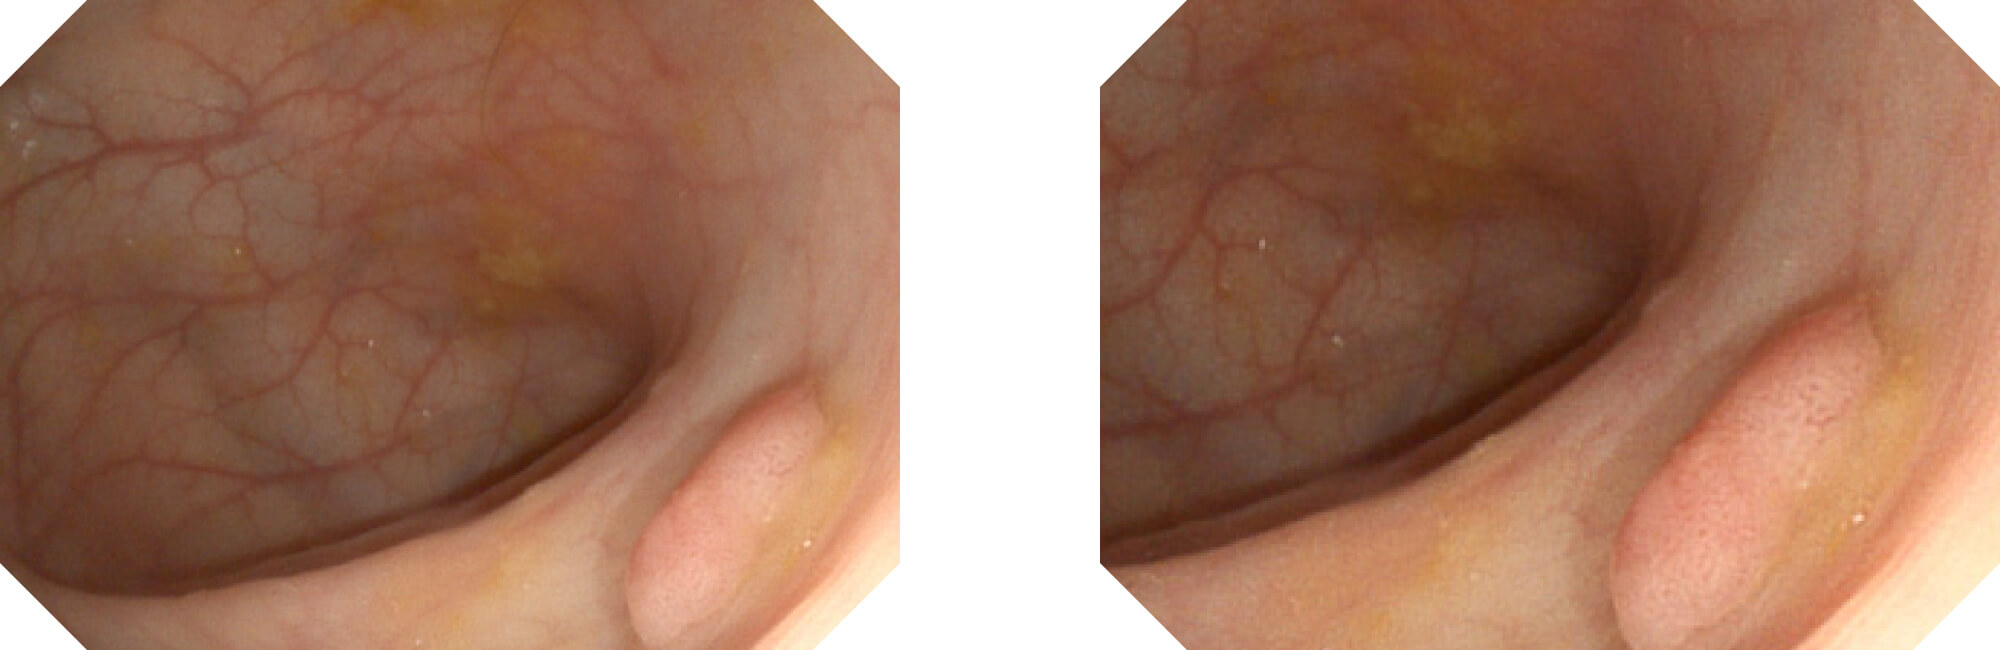

高清数字信号结合构造强调和色彩增强,多重图像处理技术能让每一个图像都清晰可见。

• 构造强调

• 色彩增强

• 电子放大